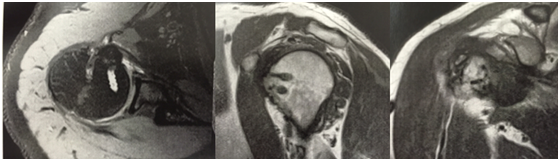

The patient was a 47-year-old man who worked as a sales representative. He presented with a history of falling down stairs two years previously, at which time he sustained trauma to the right shoulder. Since then, he had experienced pain and functional impairment, which he described as being unable to perform intimate hygiene or grab a wallet from his back trouser pocket and difficulty in using his arm when above shoulder height. The patient did not seek medical assistance at the time of the trauma because he did not have medical insurance and did not want to be treated in the public healthcare sector. Our initial physical examination showed a normal but painful range of movement; with positive tests for evaluate subscapularis tendon injury (e.g., bear-hug, Gerber, abdominal compression and lift-off tests). His DASH (Disabilities of the Arm, Shoulder and Hand) score was 60, his UCLA (University of California at Los Angeles) Shoulder Score was 16, his SF-36 (Short Form Health Survey) Score was 32.7 and his visual analog scale (VAS) score was 10. Shoulder x-rays revealed an avulsion fracture of the lesser tuberosity of the proximal humerus (Figure 1). Magnetic resonance imaging was done to support this, which confirmed the diagnosis of an isolated displaced fracture of the lesser tuberosity (Figure 2).

Figure 2 Magnetic resonance imaging showing lesser tuberosity fragment at the glenoid level (white arrow).

There is a possibility that this injury is associated with subluxation of the biceps or luxation of the long head of the biceps because of the proximity and interdigitation of the fibers of the subscapularis insertions in the humerus and superior complex of the glenohumeral and coracohumeral ligaments (i.e., the biceps pulley system), especially if the most superior part of the lesser tuberosity is also fractured .12 In our case, the fragment was dislocated by approximately 2 cm and preoperative magnetic resonance imaging showed that the fracture involved the whole tuberosity, including the most superior region. Therefore, we anticipated the reflection pulley of the biceps would also be injured, with associated dislocation of the long head of the biceps. Finally, two and a half years after the surgery, the patient in this report only had sporadic low-intensity pain, with a complete range of active and passive movements. The diagnostic tests and clinical signs for subscapularis lesions were also negative, suggesting a functional muscle-tendon unit of the subscapularis. This satisfactory outcome is consistent with existing case reports and small case series published on this topic.6-9,12